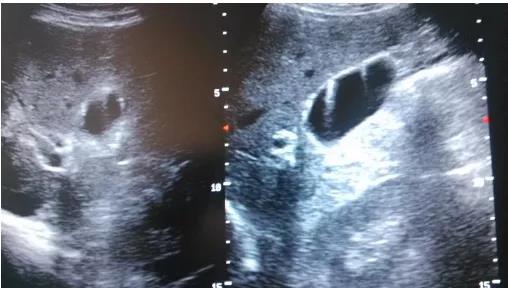

①看真假:真正可能變癌的是真息肉,假息肉不用管;

②看大小:長到1厘米了就需要考慮手術(shù),風(fēng)險大了;